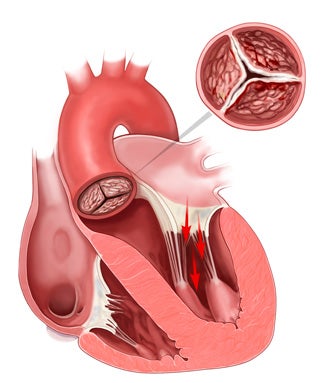

Estenose Aórtica: Valvas Cardíacas e as portas dentro do seu do Coração Imagine o seu coração como uma casa com quatro cômodos, cada um com